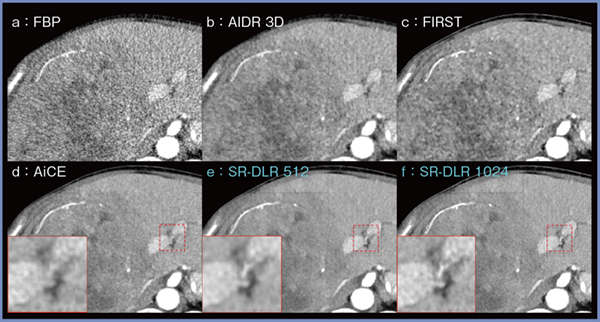

図1は,肝腫瘍症例の0.5mmスライス厚の画像における画像再構成法による画質の違いを示している。FBP(図1 a)と比較し,ハイブリッドIRの「Adaptive Iterative Dose Reduction 3D(AIDR 3D)」(b)やmodel-based IRの「Forward projected model-based Iterative Reconstruction SoluTion(FIRST)」(c)では,画質や病変の視認性は改善しているものの,ノイズがやや目立つほか,AIDR 3Dは解像度が若干劣化した印象で,FIRSTはノイズのテクスチャが乱れている。DLRである「Advanced intelligent Clear-IQ Engine(AiCE)」(図1 d)ではノイズが大幅に低減され,粒状性にも優れており,低コントラスト領域においても良好な視認性が保持されている。さらに,512マトリクスのSR-DLR 512(図1 e)は,AiCEよりもノイズ低減効果が高く,微細な構造物もより明瞭である。また,1024マトリクスのSR-DLR 1024(図1 f)では解像度がさらに向上することに加え,ノイズ特性や低コントラスト領域の視認性はAiCEと同等に保たれているように見える。

図1 画像再構成法による画質の違い(肝腫瘍,0.5mmスライス)